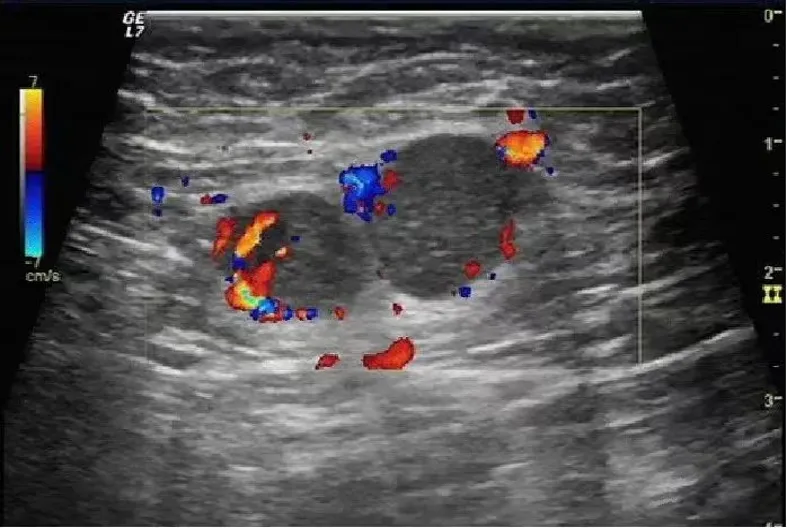

淋巴瘤

● 淋巴结不同程度肿大,多发,呈椭圆形、圆形,纵横比<2。

● 被膜清晰或不清晰,淋巴结之间可见融合。

● 皮质明显增厚呈低回声,不均匀,无液化、钙化;特征性回声改变为淋巴结内回声近似无回声的极低回声。

● 髓质变形或显示不清,或消失。

● 淋巴结内血流信号轻度或明显增多,分布杂乱;典型血流改变为淋巴结内血流信号丰富,红、蓝色血流信号充满整个淋巴结。

● 动脉血流速度加快,阻力指数正常或偏高。

淋巴瘤的血流信号在所有淋巴结中最为丰富。

淋巴结的内部回声一般表现为较均匀的低回声,当发生坏死时,其内部回声可相当低,接近无回声。